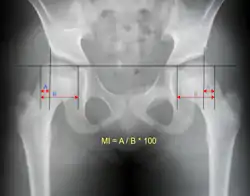

- Reimer's migration index (MI), also called the femoral extrusion index,[3] is calculated if hip dysplasia is detected. It can be used to indicate hip dislocation. It is the horizontal distance (parallel to the Hilgenreiner Line) between the Perkin line and the lateral border of the ossification center of the femoral head, divided by the horizontal width of the ossification center. The migration index is normally less than 33% by most sources,[9] but 25% and 30% has also been suggested.[10]

| Reimer's migration index[9] | ![]() |

The percentage of the femoral head that lies outside of the acetabular roof. It is also called the femoral extrusion index. | <25% |